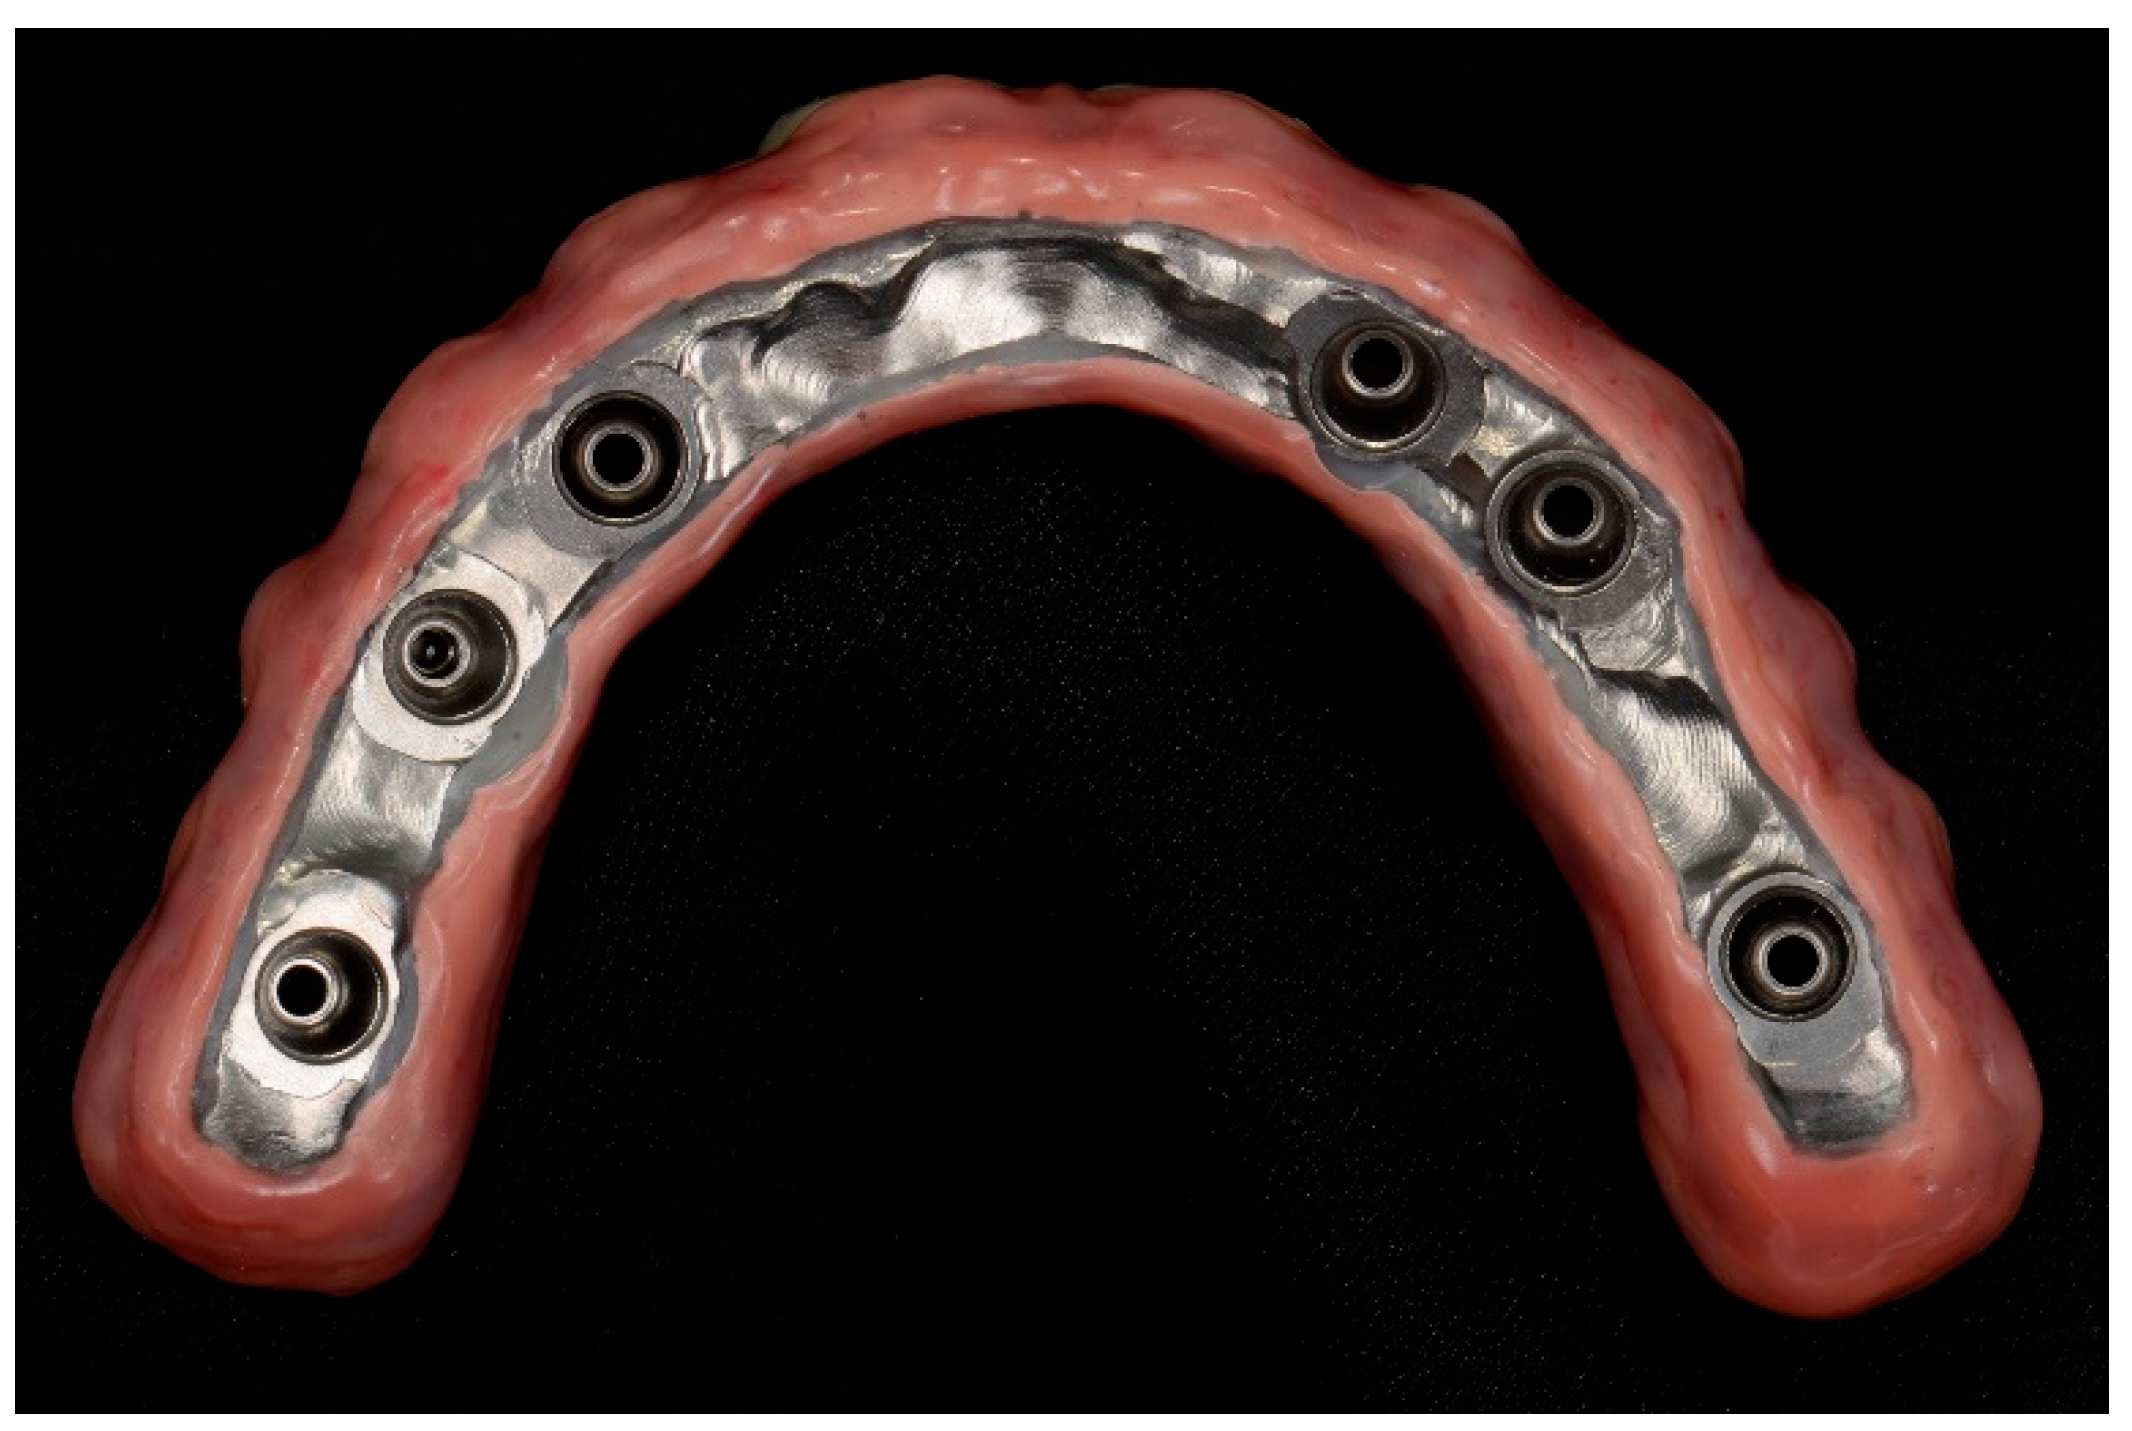

2. Materials and Methods

2.5. Prosthetic Protocol